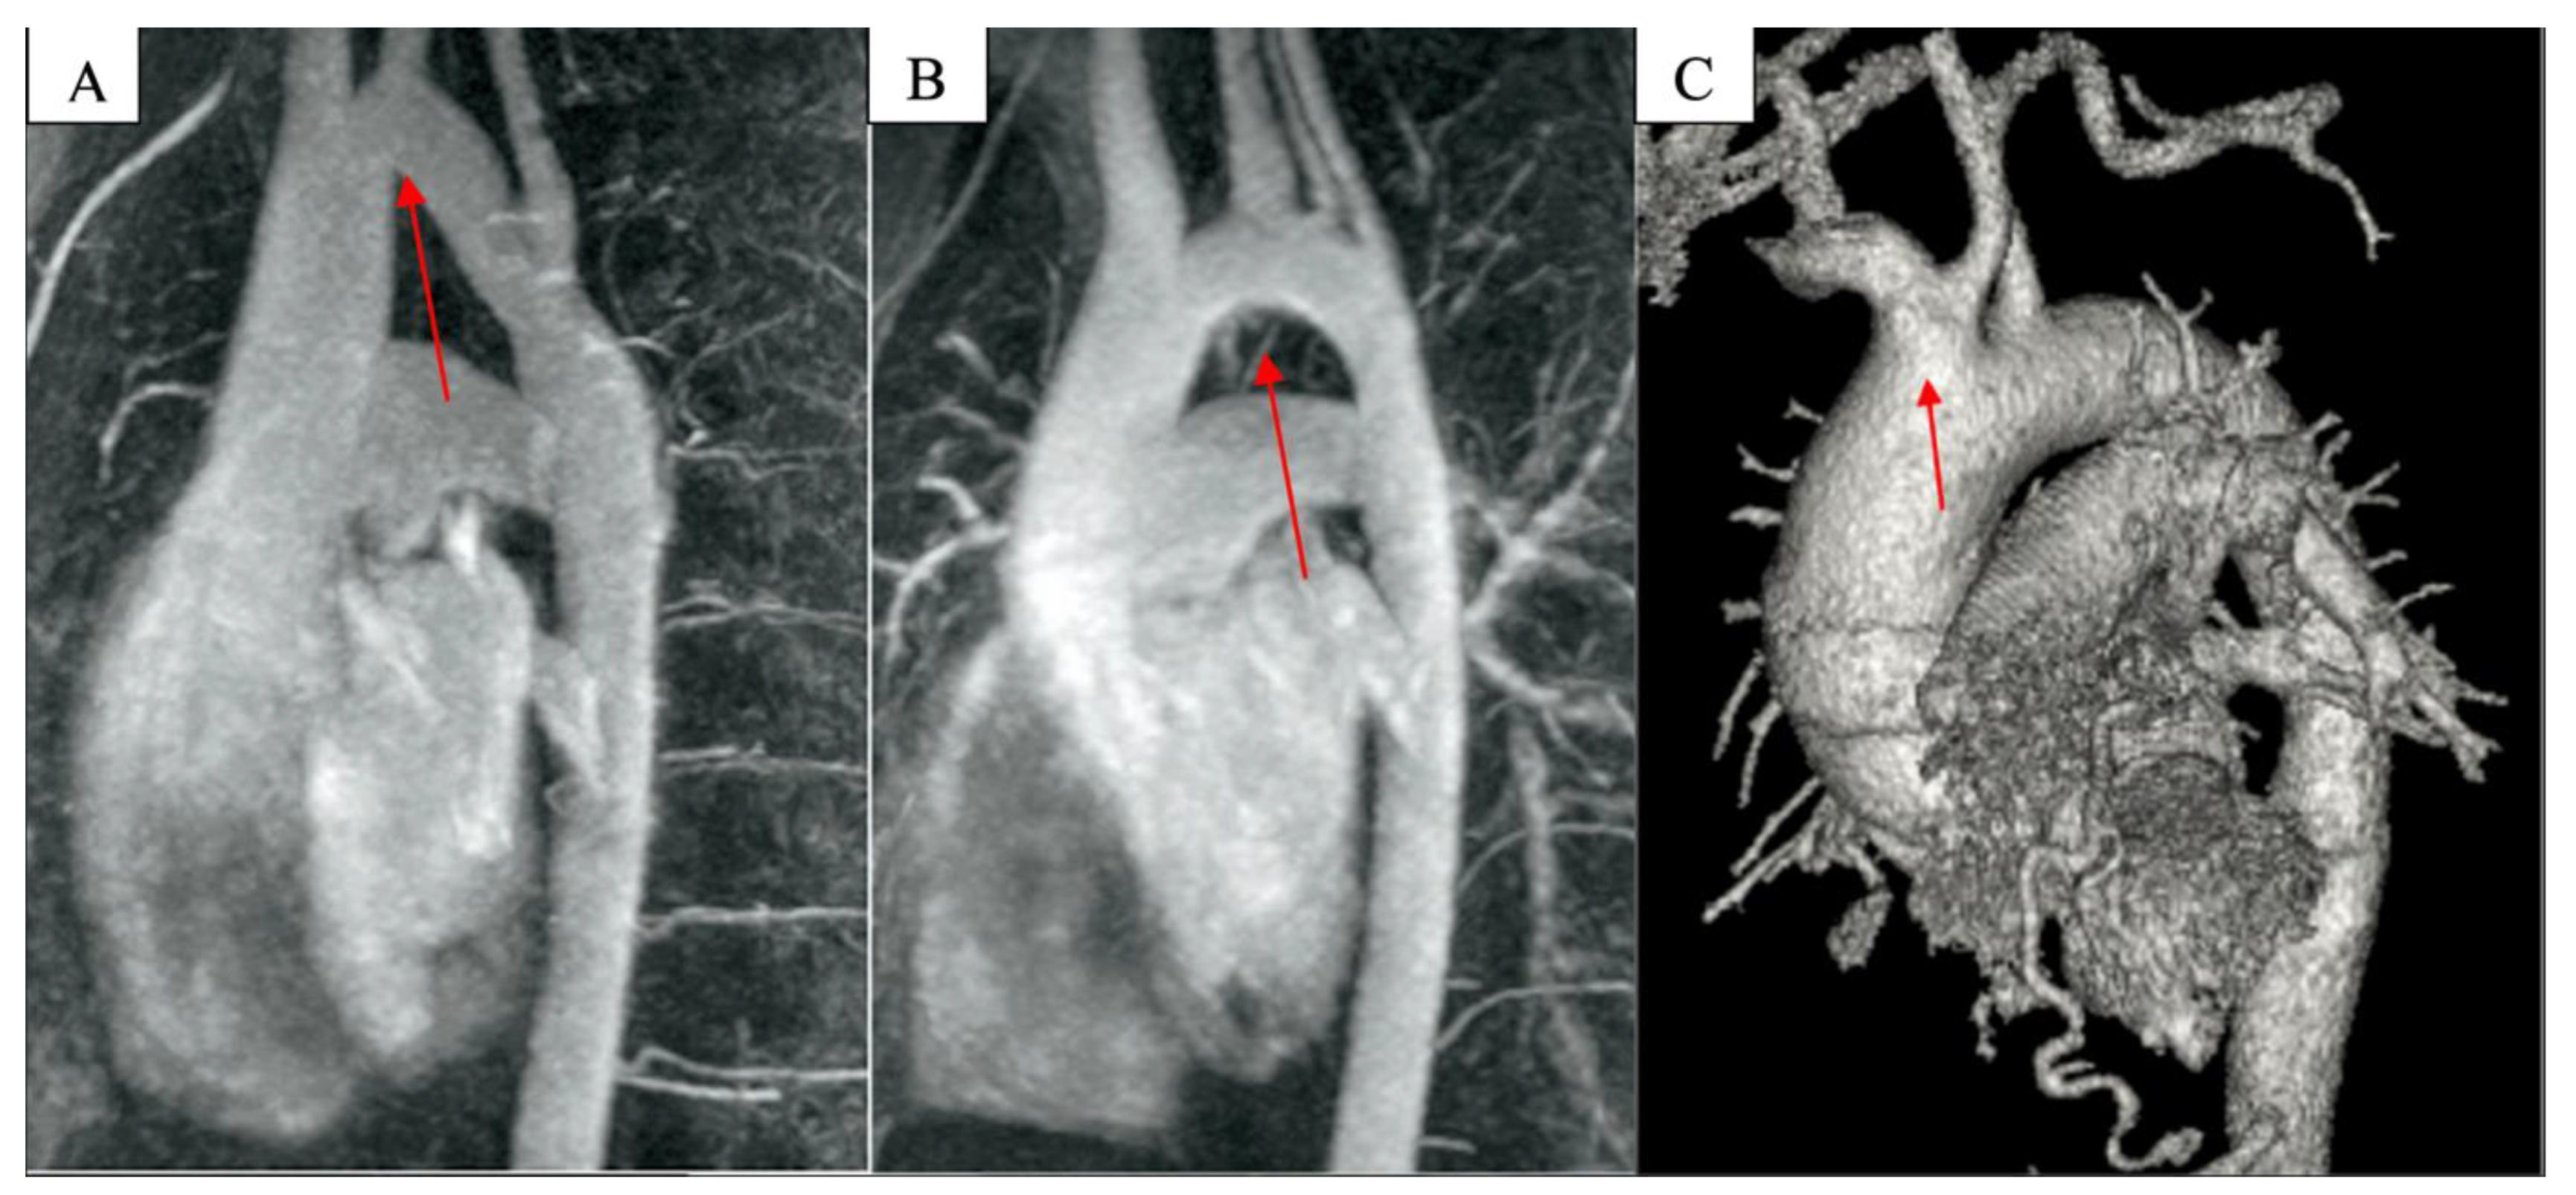

The particular arch anatomies investigated were the following (Figure 1):

Figure 1.

(A) Gothic arch, (B) Romanesque arch, and (C) bovine arch on chest CT angiography.

In addition to the hypoplastic arch, which has smaller dimensions than normal, there are patients with particular arch anatomies that are of normal sizes. These particular arch forms may include the bovine arch and Gothic, crenel, or Romanesque arches [19]. When dealing with a patient with a bovine arch, the first important step is to define and highlight this particular anatomy correctly. Turek et al. defined the bovine aortic arch based on previous definitions, as the arch features a common origin for the innominate artery and left carotid artery or features the left carotid artery originating from the innominate trunk [20]. Phalla et al. reported three types of arches based on aortic arch geometry in the left anterior oblique position: Gothic, crenel, and Romanesque. A Gothic arch is reported to have a triangular form (angulated), as seen in Gothic architecture; a crenel arch has an intermediate rectangular form; and a Romanesque arch has a smooth semicircular form (Figure 1) [21].